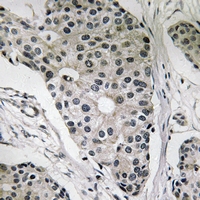

IHC (Immunohiostchemistry)

(Dilution: WB: (1/500 - 1/1000), IH (1/50 - 1/200)Immunohistochemical analysis of Leptin staining in human breast cancer formalin fixed paraffin embedded tissue section. The section was pre-treated using heat mediated antigen retrieval with sodium citrate buffer (pH 6.0). The section was then incubated with the antibody at room temperature and detected using an HRP conjugated compact polymer system. DAB was used as the chromogen. The section was then counterstained with haematoxylin and mounted with DPX.)